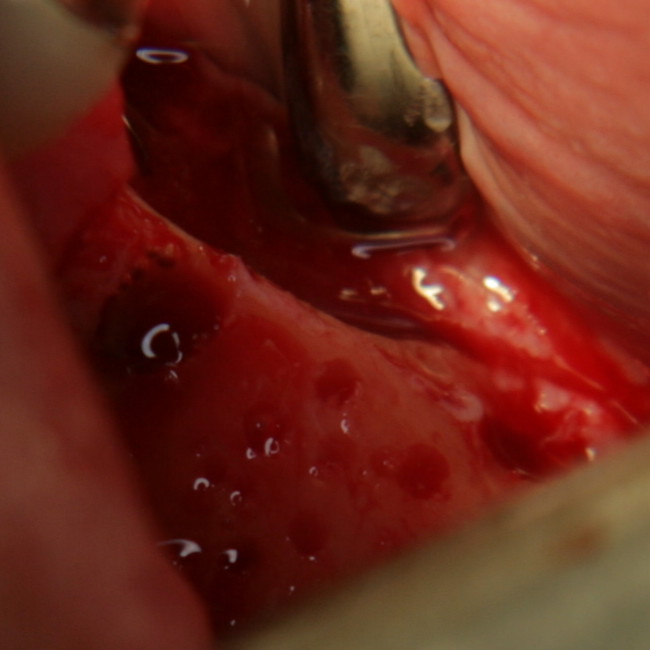

При операции с цел изграждане на допълнителн костна тъкан (костна пластика) винаги е добре да се перфорира кортикалната пластинка на костта. През тези перфорации излизат костни клетки, които постепенно прорастват в котозаместващия материал и синтезират нова костна тъкан. Перфорациите могат да се извършат с кръгло борче или с АСМ - фрезата на Neobiotech - Южна Корея.

С фрезата за автогенна кост се извършва много бързо и лесно отнемане на

кортикалната кост